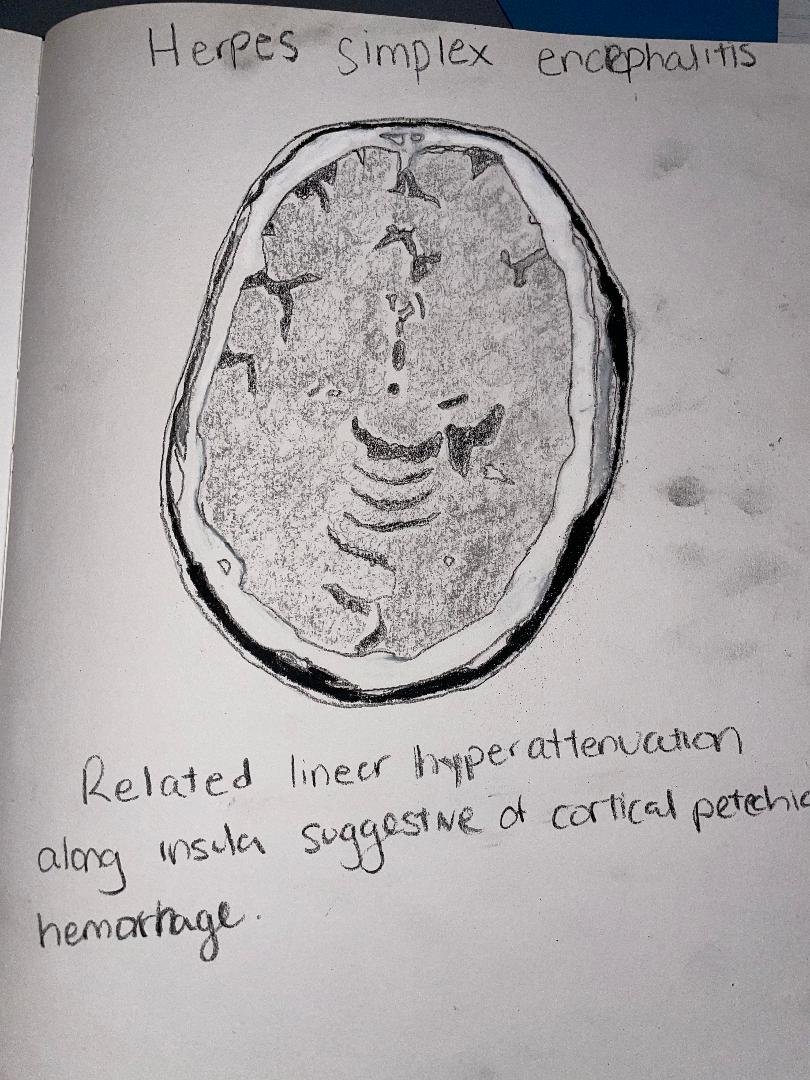

Herpes simplex encephalitis